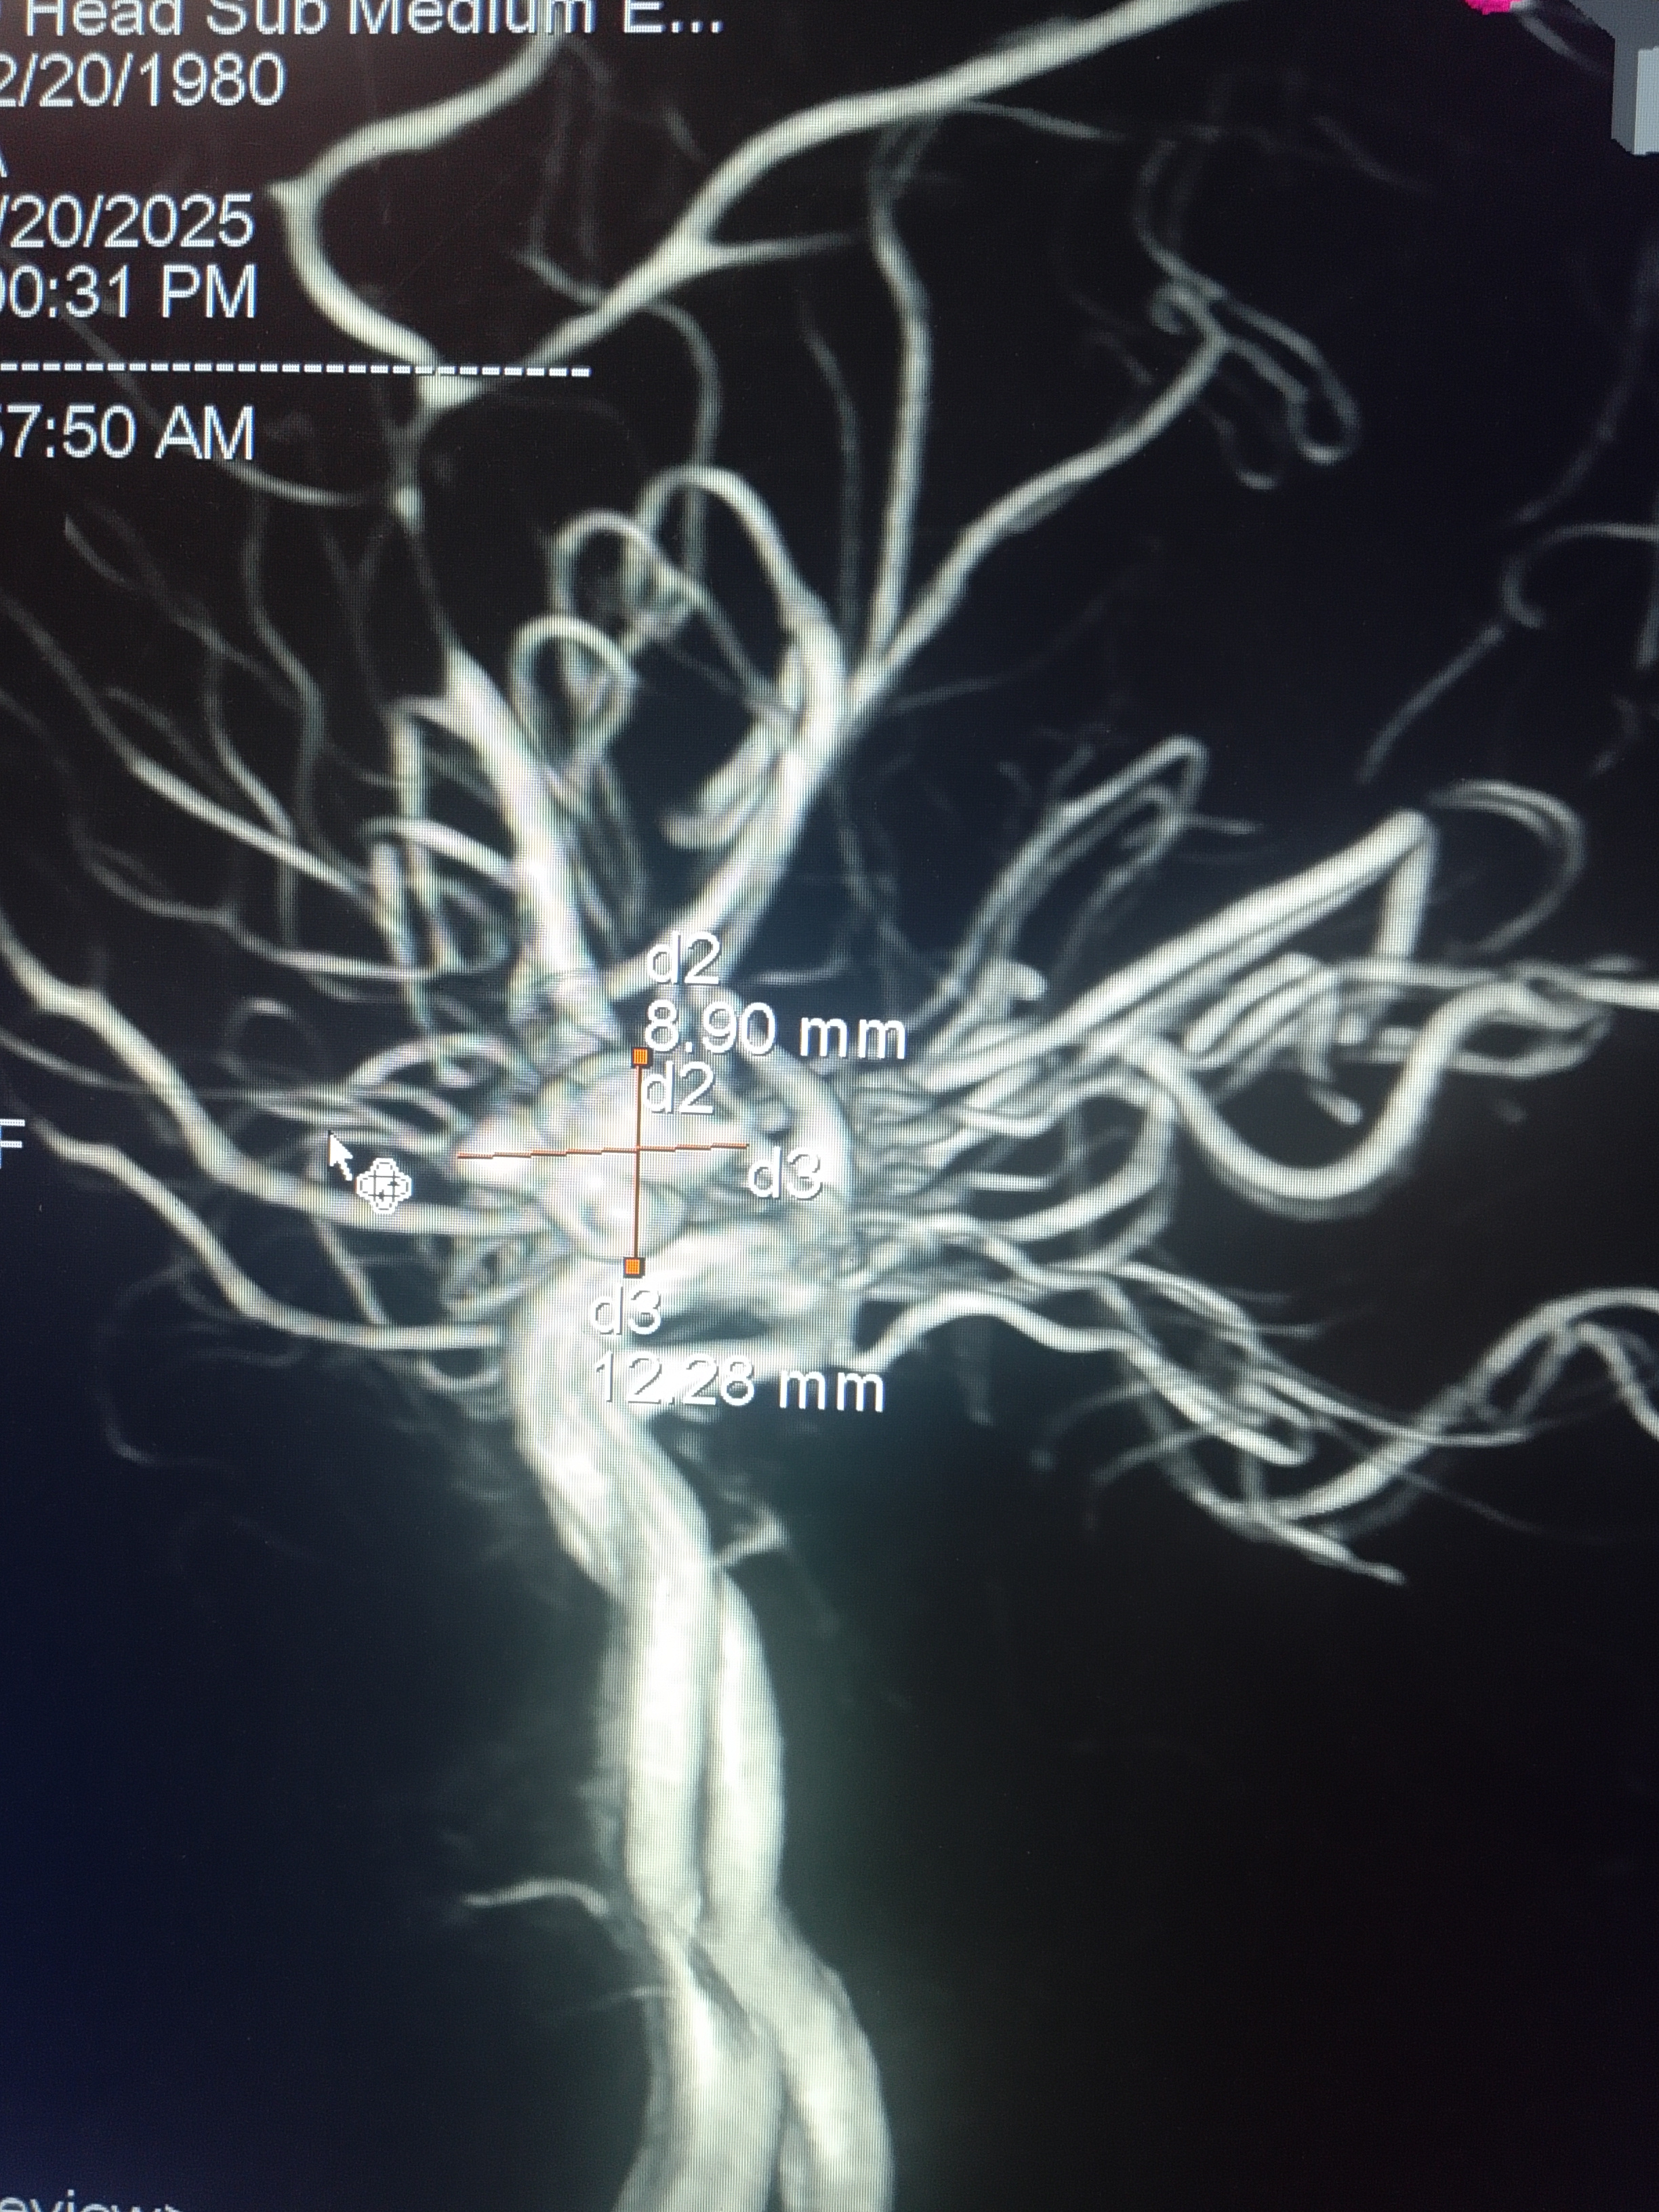

মাথা ব্যথা, ঘাড় ব্যথা, কোমর ব্যথা, পিএলআইডি সমস্যা, হেড ইনজুরি , স্পাইন ইনজুরি , স্পাইনের রড-স্ক্র ফিক্সেশন, মস্তিষ্ক - স্নায়ু - মেরুদণ্ড ব্যথা, স্পাইনাল টিউমার, ব্রেইন টিউমার, প্যারালাইসিস বা পক্ষাঘাত, স্ট্রোক, হাত - পায়ে ব্যথা, হাতে পায়ে ঝিমঝিম ভাব , শিশু নিউরোসার্জারি , ভাসকুলার নিউরোসার্জারি বিশেষজ্ঞ ও নিউরোসার্জন।